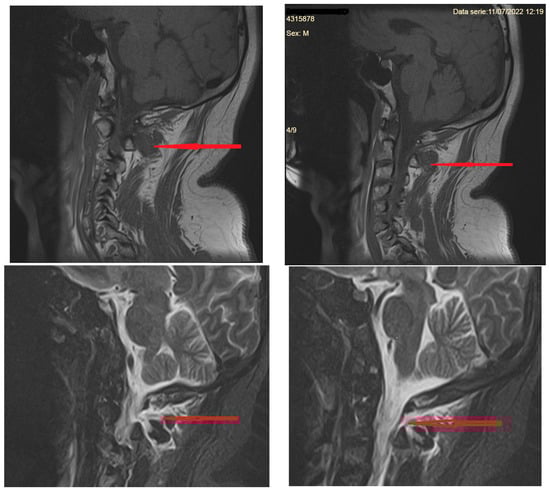

3.2.3. Imaging of the Spine

- MR imaging of the spine

- Cervical pachymeningeal enhancement

- Non-compressive spinal epidural fluid collections

- Engorgement of the epidural venous plexus

- Meningeal diverticula, dilated nerve root sleeves, that can be nonspecific unless very large and irregular [40]

- Fluid collection in soft tissues near the C1–C2 vertebrae (but which sometimes may be a false CSF leak localizing sign)

- Signs of brain sagging include flattening of the ventral pons, effacement of the prepontine and perichiasmatic cisterns, or downward displacement of the cerebellar tonsils and brain stem [5,8], which may mimic Chiari type 1 malformation. However, in SIH, the tonsils maintain normal shape and do not descend more than 5 mm below the foramen magnum [37]. Moreover, the findings associated with syringomyelia would argue for the diagnosis of Chiari type 1 malformation [32].